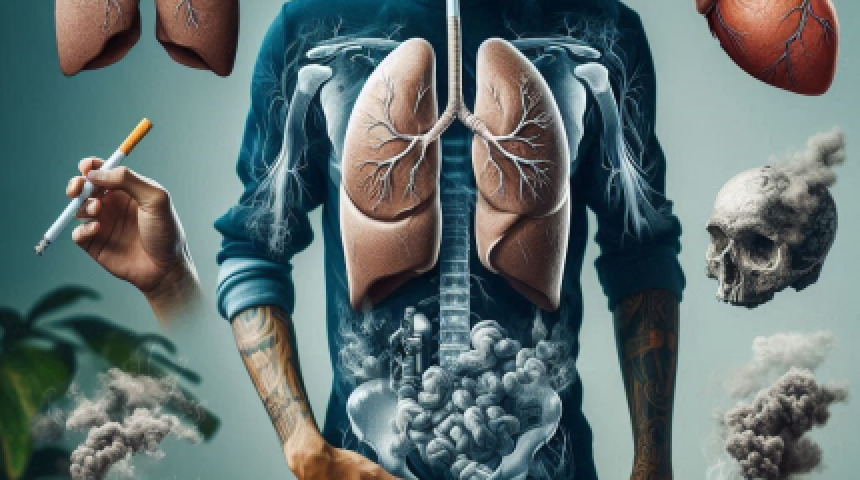

燃燒菸品與肺癌的連結性

從國健署公告的資料中可以發現,造成肺癌的六大因子中除了肺部相關疾病史以及肺癌家族病史之外,都是與燃燒有所關聯的,當中包括菸害、空氣汙染環境、特殊職場或居家環境暴露、以及炒菜油煙,這些因為燃燒而產生的恐怖致癌因子中,最常令人詬病的便是菸害。

基本上,我國國民最常接觸的致癌因子便是菸害,而其中包括了有直接吸食菸品習慣或長期吸入二手煙。國外的實驗數據顯示,菸草燃燒後產出的煙霧中所含焦油會破壞肺部和氣管細胞,令肺部纖毛失去排污的功能,增加患上支氣管炎、肺氣腫以及肺癌的機會。因此吸菸者罹患肺癌的機會遠比非吸菸者高,將近十倍!這點從肺癌患者中有高達八成是吸菸人士亦可得到證實。

二手煙的危害卻也沒有比直接吸食菸品低多少,台灣所有菸品市占率仍是紙菸獨占鰲頭,擁有超過八成的市占率,因此大部分的二手煙都是來自紙菸燃燒產出以及吸菸者吸食菸品時吐出。據調查結果顯示,吸菸者的配偶因經常吸入二手煙,罹患肺癌的風險比一般人高出三成,患支氣管炎、慢性呼吸系統疾病、心血管病的風險亦會增加。兒童若長期暴露於二手煙的環境下可能罹患過動症、憂鬱或躁鬱症等,若是嬰兒吸到二手煙甚至可能猝死!

燃燒是肺部最大的敵人,向「燃燒」說不

其實如同本文開頭所說,燃燒與肺癌有著息息相關的關係。吸菸者若能戒菸當然是最好的,政府這些年對於打擊菸害也十分積極,大幅宣導菸害的嚴重性並提供戒菸門診服務鼓勵菸民戒菸,如此便能讓自己的肺遠離燃燒;若是真沒有戒菸打算,也可嘗試尋找不須燃燒便能使用的菸品作為替代品,在最新的菸害防制法修正草案三讀通過後,相信不久後這些非燃燒的菸品便可在市面上合法販售,也不失為一個新的選擇。